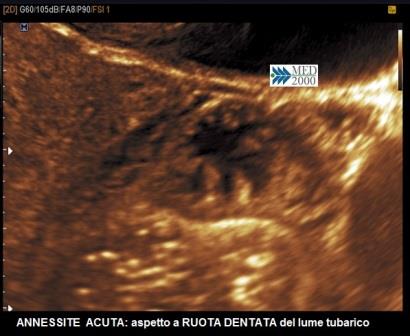

Annessite acuta

Il segno ecografico caratteristico delle fasi iniziali è la presenza di una tumefazione annessiale adiacente all'ovaio, isoecogena col miometrio, di forma tubulare o ovoidale, non sempre facilmente distinguibile dall'intestino; un operatore esperto può coglierne i segni distintivi: assenza di peristalsi, dolore evocato dalla pressione mirata con la sonda endocavitaria (pain mapping), presenza di una discreta o ricca vascolarizzazione al color/power Doppler. Successivamente, con la formazione di una piosalpinge, la tuba si distende assumendo una morfologia tubuliforme per la presenza di liquido ad aspetto ipoecogeno, disomogeneo, dovuto all'accumulo di pus e sangue e la parete tubarica si ispessisce per l'edema conseguente alla flogosi; alcuni Autori hanno proposto un cut-off di 5 mm. per indicare l'ispessimento della parete tubarica, mentre altri si rifanno all'impressione soggettiva dell'ecografista. In sezione trasversa si osservano delle protrusioni endoluminali iperecogene legate all'edema delle pliche endosalpingee che danno origine ad un segno ecografico caratteristico, il "segno della ruota dentata".

Sempre in sezione trasversa è possibile individuare dei setti incompleti spessi che non raggiungono la parete tubarica opposta. Questo segno non sembra essere caratteristico delle forme acute in quanto è possibile osservarlo anche nelle idrosalpingi.